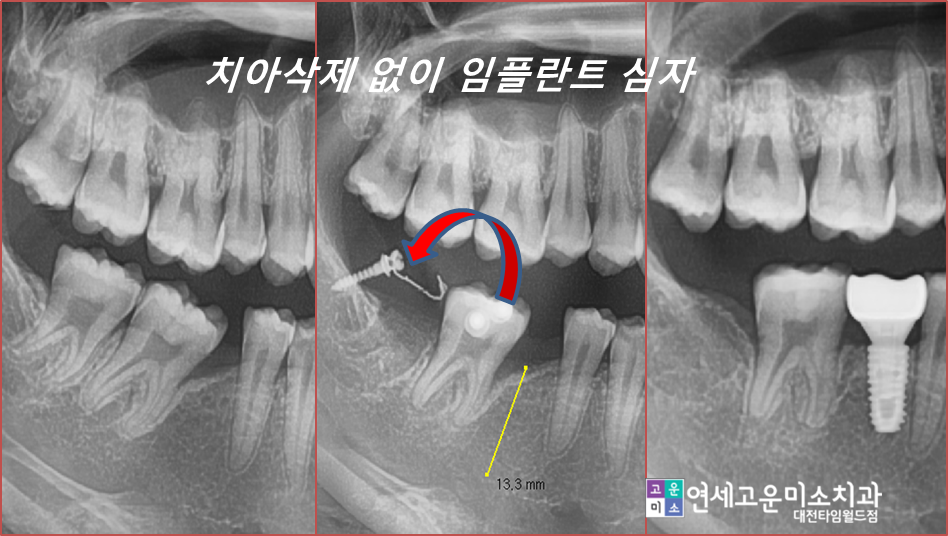

이런 경우 간단한 부분교정으로

해결할 수 있습니다

사랑니를 발치하고 간단한 교정장치를

이용하여 쓰러진 두 번째 큰 어금니를 세웠습니다

기간은 6개월 정도 소요되었습니다

완성된 모습입니다

옆치가 원래 각도 모습으로

잘 세워져있고

임플란트도 옆 치아의 뿌리와 나란히

잘 위치해 있는 것을 확인할 수 있습니다.